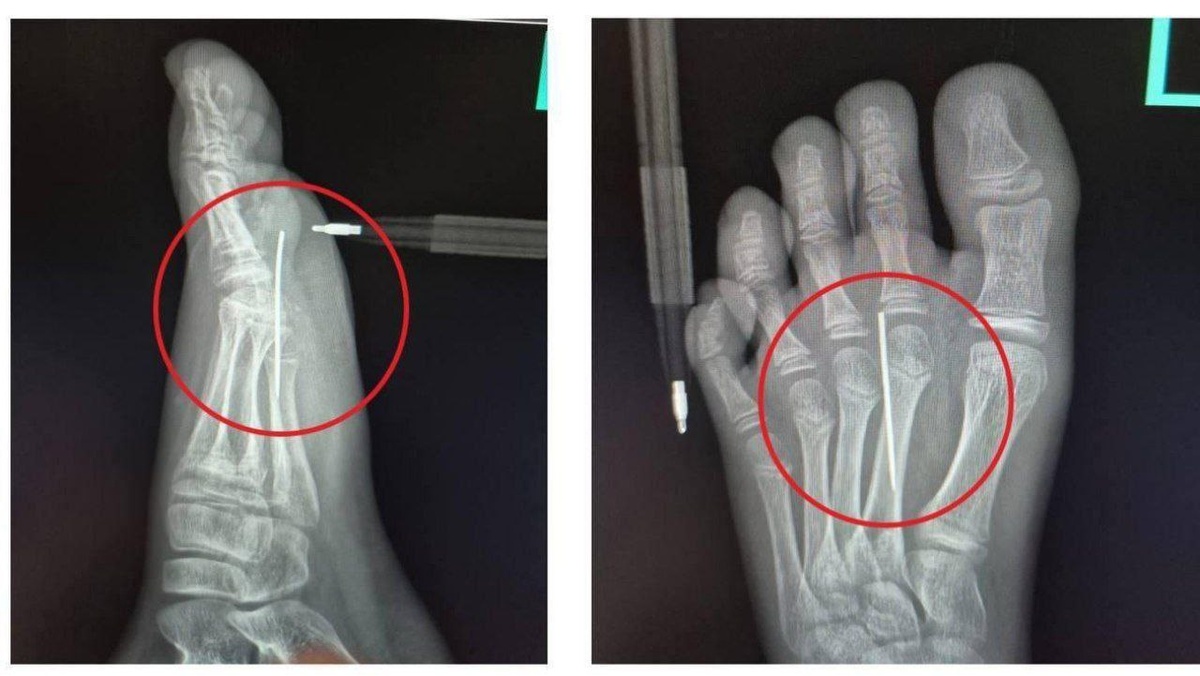

Поиграл в кальмара! В Подмосковье мальчик поранился, пытаясь повторить испытание с печеньем. 10 - летний парнишка вырезал фигурки иголкой, и в итоге сам стал жертвой “игры” - игла полностью вонзилась в его стопу! Спасать его пришлось врачам Детского клинического центра имени Рошаля, которые оперативно извлекли инородное тело из его ноги.

10 - летний парнишка вырезал фигурки иголкой, и в итоге сам стал жертвой “игры” - игла полностью вонзилась в его стопу!

Спасать его пришлось врачам Детского клинического центра имени Рошаля, которые оперативно извлекли инородное тело из его ноги.